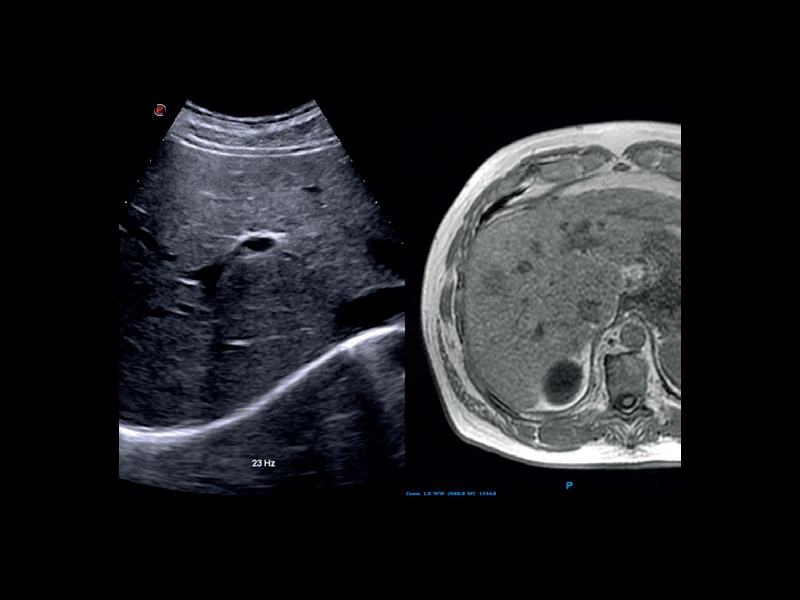

MyLab™E80 - VNav - Liver Fusion

MyLab™E80 - VNav - Liver Fusion

MyLab™E80 - LiverFusion

MyLab™E80 - LiverFusion